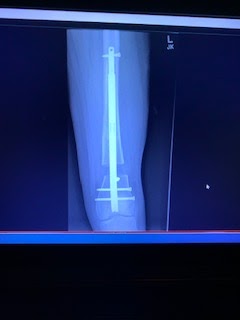

The bottom of her femur and the entire rod.

You can see how much we've lengthened; 20.14 mm  or .79 inch. Its amazing!